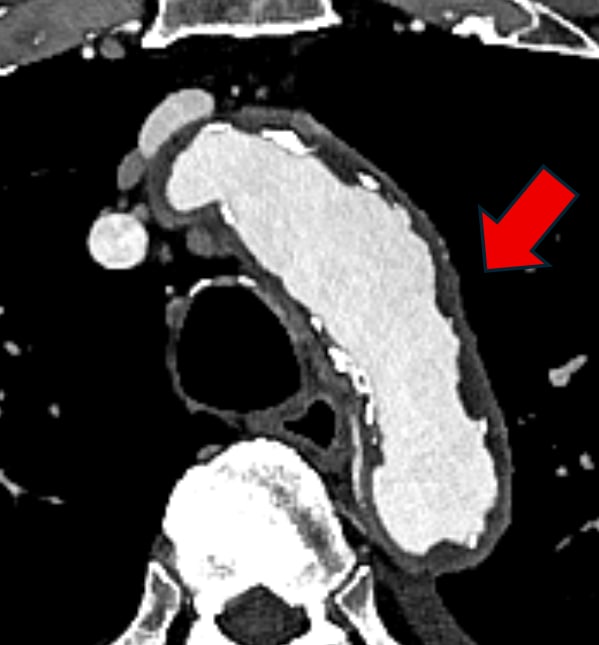

図1.大動脈造影CT水平断

弓部大動脈 (→)の内腔に、5mm以上の厚みのある不整な粥腫が認められる。いわゆるshaggy aortaである。一部に点状の石灰化が認められる。

明らかな動脈瘤や上行大動脈の全周性壁石灰化は認めない。